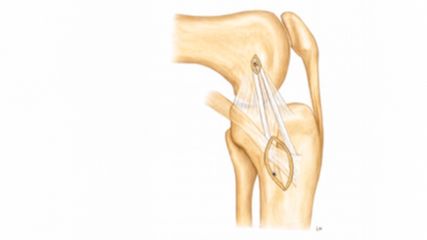

This new technique allows for the first time to investigate the 3D morphology of hip deformities based on MRI (Fig.4). Using this technology enabled us to quantify the size of the articular surface and demonstrate that the severely retroverted acetabulum does not actually represent a deep hip. Instead hips with acetabular retroversion present a smaller articulating cartilage surface area but a comparably large non-articulating fossa acetabularis (Fig. 4). This finding supports anteverting periacetabular osteotomy over acetabular rim trimming in order to prevent iatrogenic hip dysplasia. Furthermore, we could quantify the adaptive hypertrophy of the acetabular labrum in hip dysplasia compared to hips with a normal acetabulum and pincer-type hips. A fast and reliable individual analysis of cartilage and labrum surface area compared to surface area of the non-articulating fossa acetabularis yields unprecedented ways to characterize hip morphology with the goal to improve surgical planning on a routine basis. Furthermore, a fully automated volumetric analysis of cartilage composition using 3D dGEMRIC maps may aid surgeons when contemplating.

Fig. 4: Demonstrated are 3D models of pelvic bone with cartilage (blue) and labrum (red) of three different hip pathologies. Relative surface area of cartilage and the fossa is defined as the absolute surface area of cartilage divided by the absolute surface area of the femoral head. Labral contribution is defined as the absolute surface area of the labrum divided by the surface area of the joint contact surface (surface area labrum + cartilage)